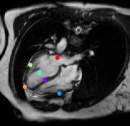

Datasets: A set of isotropic mm MR scans were obtained from the ADNI database [10] to evaluate the proposed method. While, a subset of and images are used for training and testing. All brain images were skull stripped and affinely aligned to the MNI space, thus allowing ground truth planes to be extracted in the standard directions. For cardiac images, we use short-axis cardiac MR of resolution mm obtained from the UK Digital Heart Project [8]. A subset of and images are used for training and testing. ACPC planes are evaluated using the AC and PC landmarks for the distance error calculation. Similarly, we use the outer aspect, inferior tip and inner aspect points of splenium of corpus callosum for mid-sagittal planes. For cardiac MRI, we use six landmarks projected on the 4-chamber plane; the two right ventricle (RV) insertion points, right and left ventricles (LV) lateral wall turning points, apex, and the center of the mitral valve, See Fig. 2.